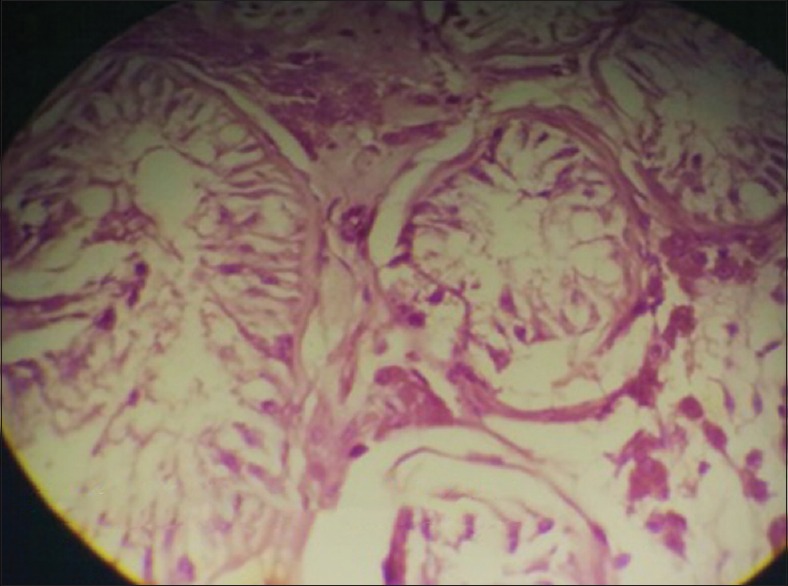

持续性苗勒管综合征(PMDS)是一种罕见的男性假两性畸形,其特征是在46,XY核型的正常男性中存在苗勒管结构。横向睾丸异位(TTE)是一种罕见的睾丸异位形式,其中两个睾丸位于腹股沟一侧。对侧阴囊是空的。经前综合症合并TTE是罕见的。我们报告一个25岁男性右腹股沟疝手术中发现的经前症候群伴TTE的病例。

Persistent Mullerian duct syndrome (PMDS) is a rare form of male pseudohermaphroditism characterized by the presence of Mullerian duct structures in a normal male with 46, XY karyotype. Transverse testicular ectopia (TTE) is rare form of testicular ectopia in which two testes are located on one inguinal side. The opposite scrotum is empty. PMDS with TTE is rare. We report a case of PMDS with TTE discovered during surgery for a right inguinal hernia in a 25-year-old male.